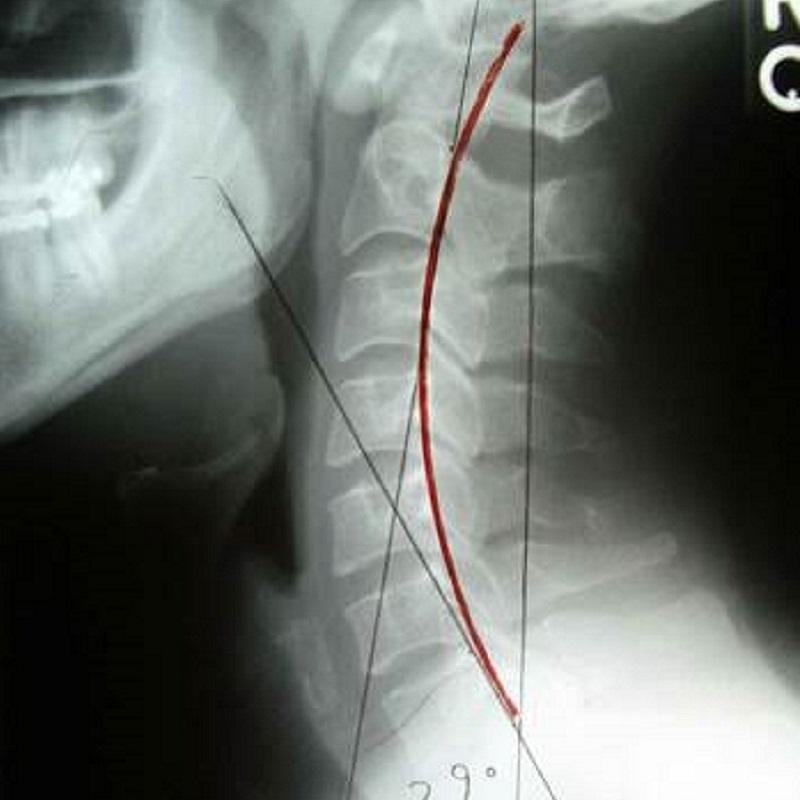

頸椎由七塊頸椎骨組成,範圍由髗底至背上端胸椎連接處:不典型頸椎(包括第一、二頸椎),典型頸椎(包括第三至七 頸椎),不同節段頸椎會共同參與頸運動,包括前屈後伸、左右傾斜及兩側旋轉的生理動作。頸椎骨有由上而下編排數目,例如頸一或簡稱C1;對於相連兩節頸椎標示,檢查報告會示 / 標記,例如C5/6 就代表頸椎骨第五及六之間處位置。明白數字標注會方便理解顯像報告所指位置。

在功能方面,頸椎除支持頭部重量外,更負責協調頭部動作,配合頭部感官器官眼、耳、口、鼻感受環境變化及急機。致病原因如運動創傷或肌肉勞損都可以引起頸痛,寒背姿勢、工作壓力亦可促使頸痛發作。論病理發展,頸部肌肉、韌帶等軟組織傷患與頸椎關節疾患又可以互為因果引致痛症,嚴重者頸正常生理弧度拉直或反張。更甚者,長期頸痛往往伴隨抑郁等情緒病發作。

上頸椎病變可引致上頸椎神經根受壓或產生神經炎症,刺激枕大神經及枕小神經,導致後枕痛、頭側顳部或眉梭位置疼痛,甚或引發張力性頭痛。頸源性頭痛症狀包括頭後枕部牽拉感、頭皮刺痛,上頸椎有相應頸椎錯位或移位,X光張口位檢查亦可上頸椎表現旋轉、偏側或偏移等現象。(延伸閲讀頭痛篇章)